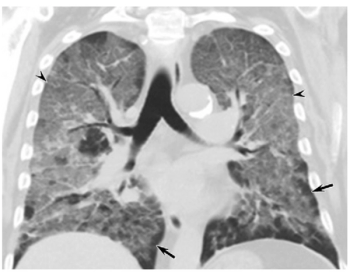

Chest MRI picks up the same characteristics of COVID-19 pneumonia that are seen on chest CT, making it a good alternative without the radiation.

Findings from a French study contradict recommendations from the American College of Radiology and the international community against using chest CT scans an initial tool for viral diagnosis.